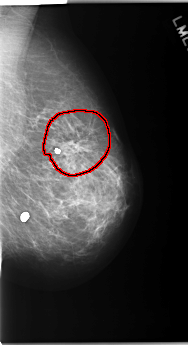

FILE: C_0171_1.LEFT_MLO.OVERLAY

TOTAL_ABNORMALITIES 1

ABNORMALITY 1

LESION_TYPE MASS SHAPE ARCHITECTURAL_DISTORTION MARGINS SPICULATED

ASSESSMENT 2

SUBTLETY 5

PATHOLOGY BENIGN

TOTAL_OUTLINES 1

BOUNDARY